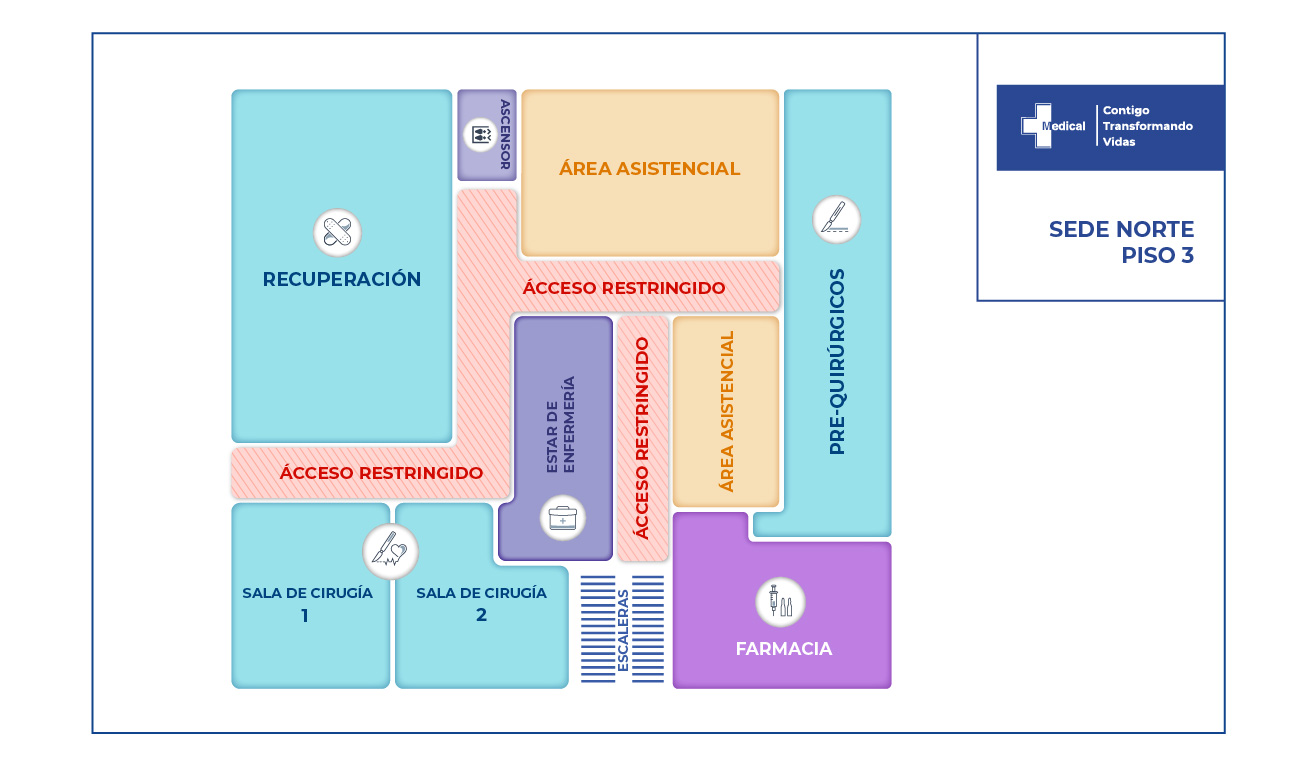

La condición de ingreso es realmente poco alentadora, sin embargo la oportunidad de los servicios, la eficiencia y eficacia que caracteriza a la clínica Medical SAS, ofrece al paciente y su familia todo un equipo interdisciplinario para la atención adecuada y secuencial para este tipo de traumas. Precedida por especialistas en cirugía general, neurocirugía, psicología, psiquiatría, servicios de apoyo terapéutico y radiológico, salas de cirugía, unidad de cuidados intensivos, rehabilitación física, clínica de heridas, entre otros.

El paciente fue sometido a 3 cirugías y 6 procedimientos realizados entre cirugía general como tratamiento a través de toracostomia, de igual manera descarto lesiones abdominales por trauma cerrado y neurocirugía realiza la reparación de la fistula espinal de líquido cefalorraquídeo, la reducción abierta de fractura de columna vertebral y artrodesis de la región torácica (consistió en la colocación de 20 tornillos transpediculares, 2 barras verticales y 1 conector transverso, esto en 10 segmentos).